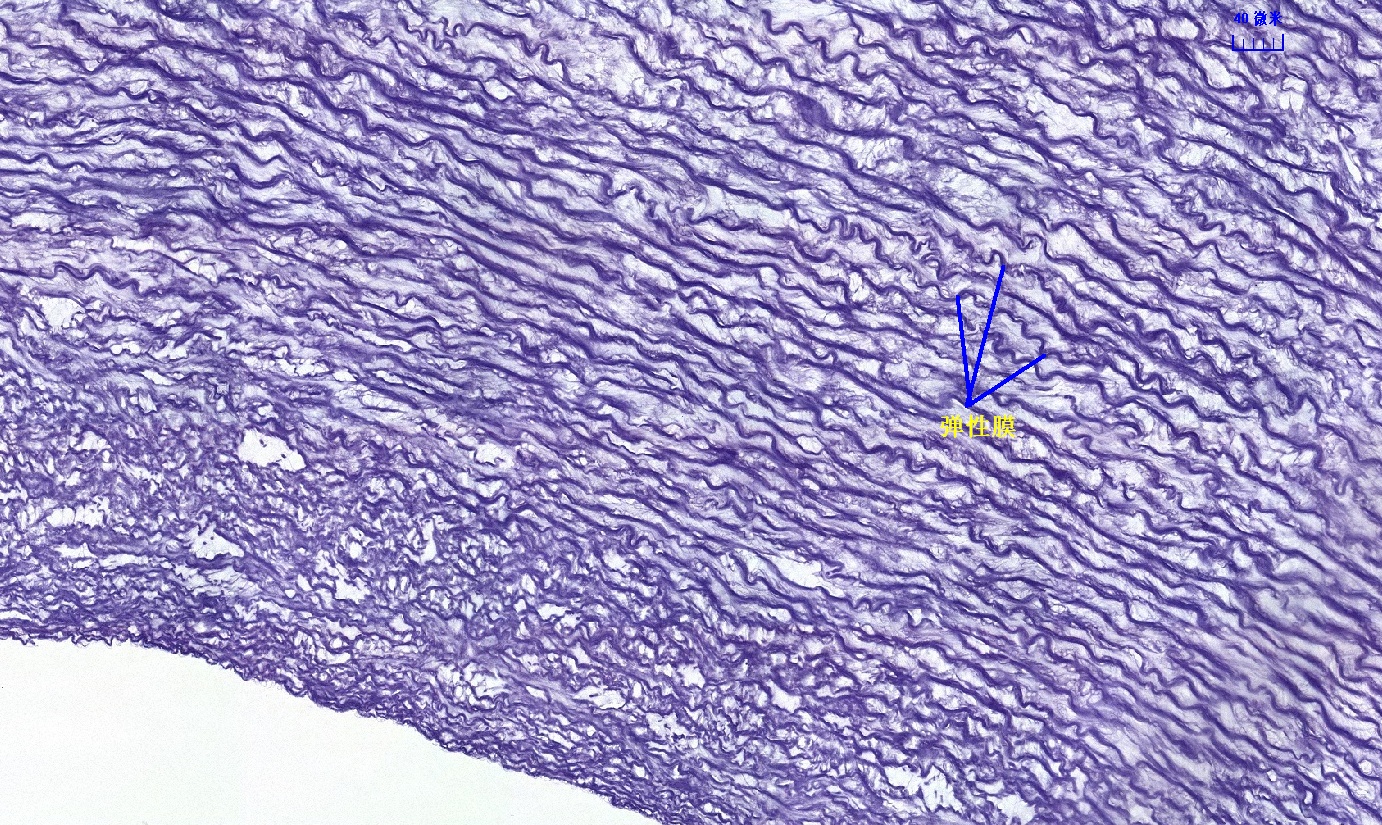

6.1 循环系统切片库